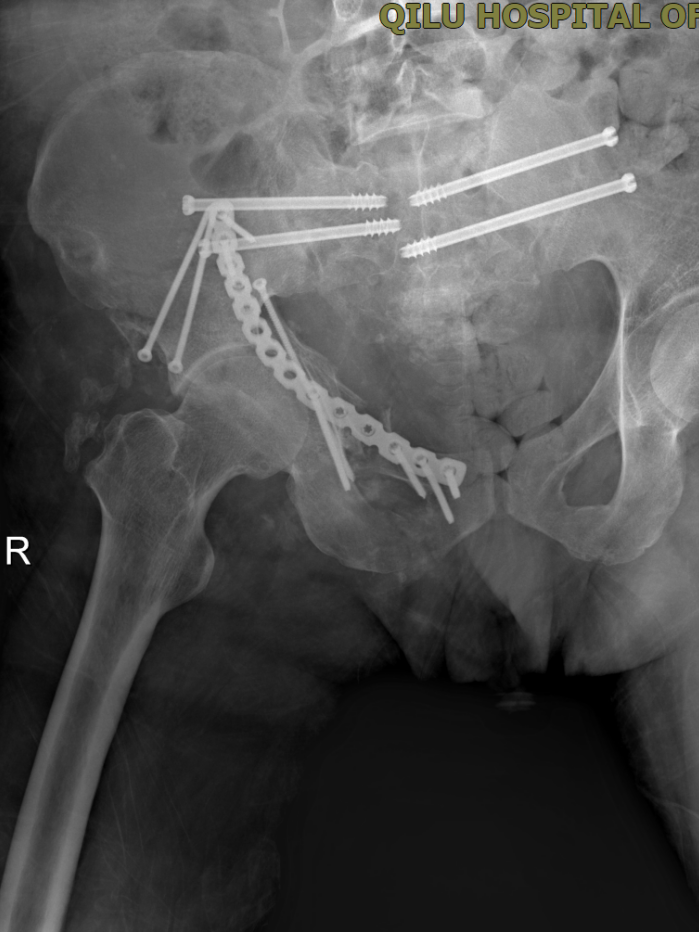

3月13日,一场高难度的骨盆重建手术率先展开。 因患者整个骶骨粉碎性骨折移位明显,血压和身体状况无法耐受开放性大手术,且患者骨性结构破坏严重,置钉极为困难。主刀医生刘涛主任反复调整、精细操作,最终成功置入4枚骶髂螺钉,固定稳定可靠,带领急诊外科团队成功完成了手术。

3月24日,团队再次实施右髋臼陈旧性骨折切开复位内固定术+股神经探查松解术+抗生素人工骨植入术,实现骨折修复、神经松解、感染预防三大目标。

骨折终极固定术后复查影像3月25日,距离入院整整27天,在多学科团队的日夜坚守下,患者顺利转出ICU,进入普通病房接受康复治疗。转出前,患者意识清醒、精神良好,已停用所有血管活性药物,呼吸、循环稳定,血氧饱和度持续99%,双肺无明显感染体征,曾经濒临崩溃的生命重焕生机。